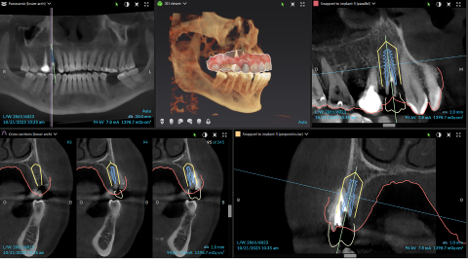

During your initial consultation at Arcadia Perio, Dr. Peterson will review your medical history, perform an oral exam, take digital X-rays, and likely consult your general dentist. Sometimes, a 3D scan is taken with our cone-beam computed tomography scanner to accurately visualize your unique anatomy and plan virtual implant treatment. The initial planning phase is as thorough as possible to optimize long-term success and determine your optimal solution.

Procedure & Same-Day Teeth

The 3D image we took during your consultation is used to create computer-aided guidance with our sophisticated X-Nav system. Visualizing the placement of your dental implants in 3D eliminates guesswork and potential complications. In the skilled hands of Dr. Peterson, proper planning combined with X-Guide Dynamic 3D Navigation during surgery elevates surgical excellence while increasing efficiency and safety. If you received full-mouth dental implants, our customized, streamlined protocol enables Dr. Peterson to fit you with temporary 3D-printed teeth within 24 hours of your surgical procedure.

Implant Treatment Planning

Clinical overview

3D planning

CBCT & planning

Planning detail

Additional planning view